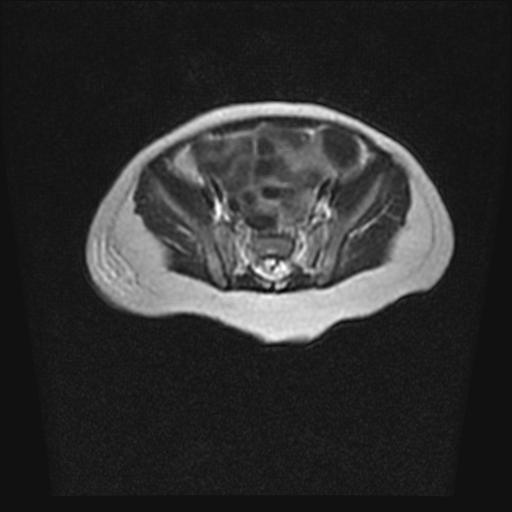

四个月的女婴,ct示脊膜膨出.

脊柱裂、脊膜膨出,请结合临床除外皮毛窦。

脂肪脊髓脊膜膨出

脊柱裂、脊膜膨出